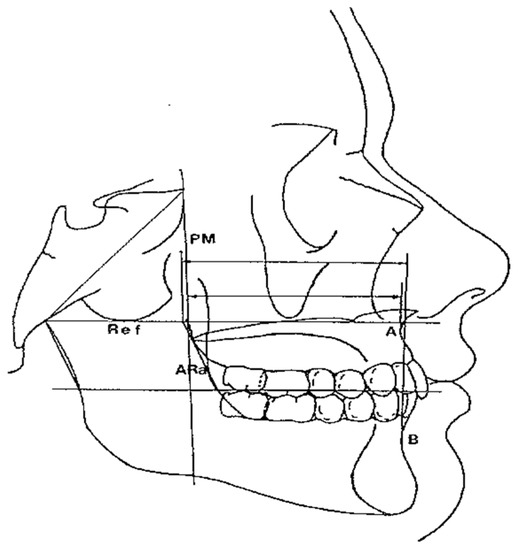

- Maxillary and Mandibular skeletal arches (Figure 1): this parameter compares the lengths of the maxillary and mandibular skeletal arches. The maxillary skeletal arch was measured by the distance between A point and PM, in parallel with Ref. The mandibular skeletal arch was measured by the distance between the orthogonal projection of B point on Ref and ARa, at its intersection point with Ref.

- Maxillary and Mandibular dento-alveolar arches (Figure 2): this parameter compares the lengths of maxillary and mandibular dento-alveolar arches. The maxillary dental arch was measured by the distance between PM and SPr, in parallel with Ref. The mandibular dental arch was measured by the distance between the orthogonal projection of IPr on Ref and Ara, at its intersection point with Ref.

- Middle Cranial Floor (MCF) and Mandibular ramus (Figure 3): this parameter compares the horizontal dimension of the middle cranial floor (Ar to neutral PM) and the width of the ramus (Ar to ARa). These parameters were measured along the Ref.